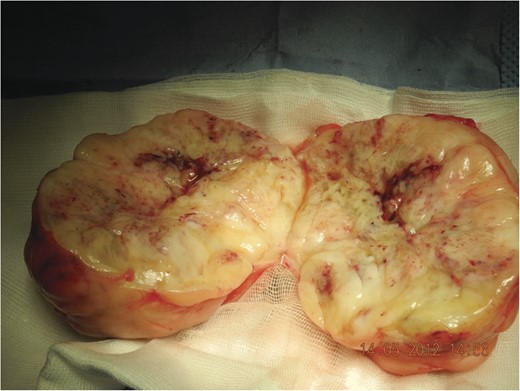

During surgery a large yellow lobular partially fibrotic mass (Fig. 2) was excised located entirely above the muscle fascia. Histological examination showed nodular fasciitis without signs of malignancy.

Tumour ex vivo, note the lobular structure with fibrous septa (incised).